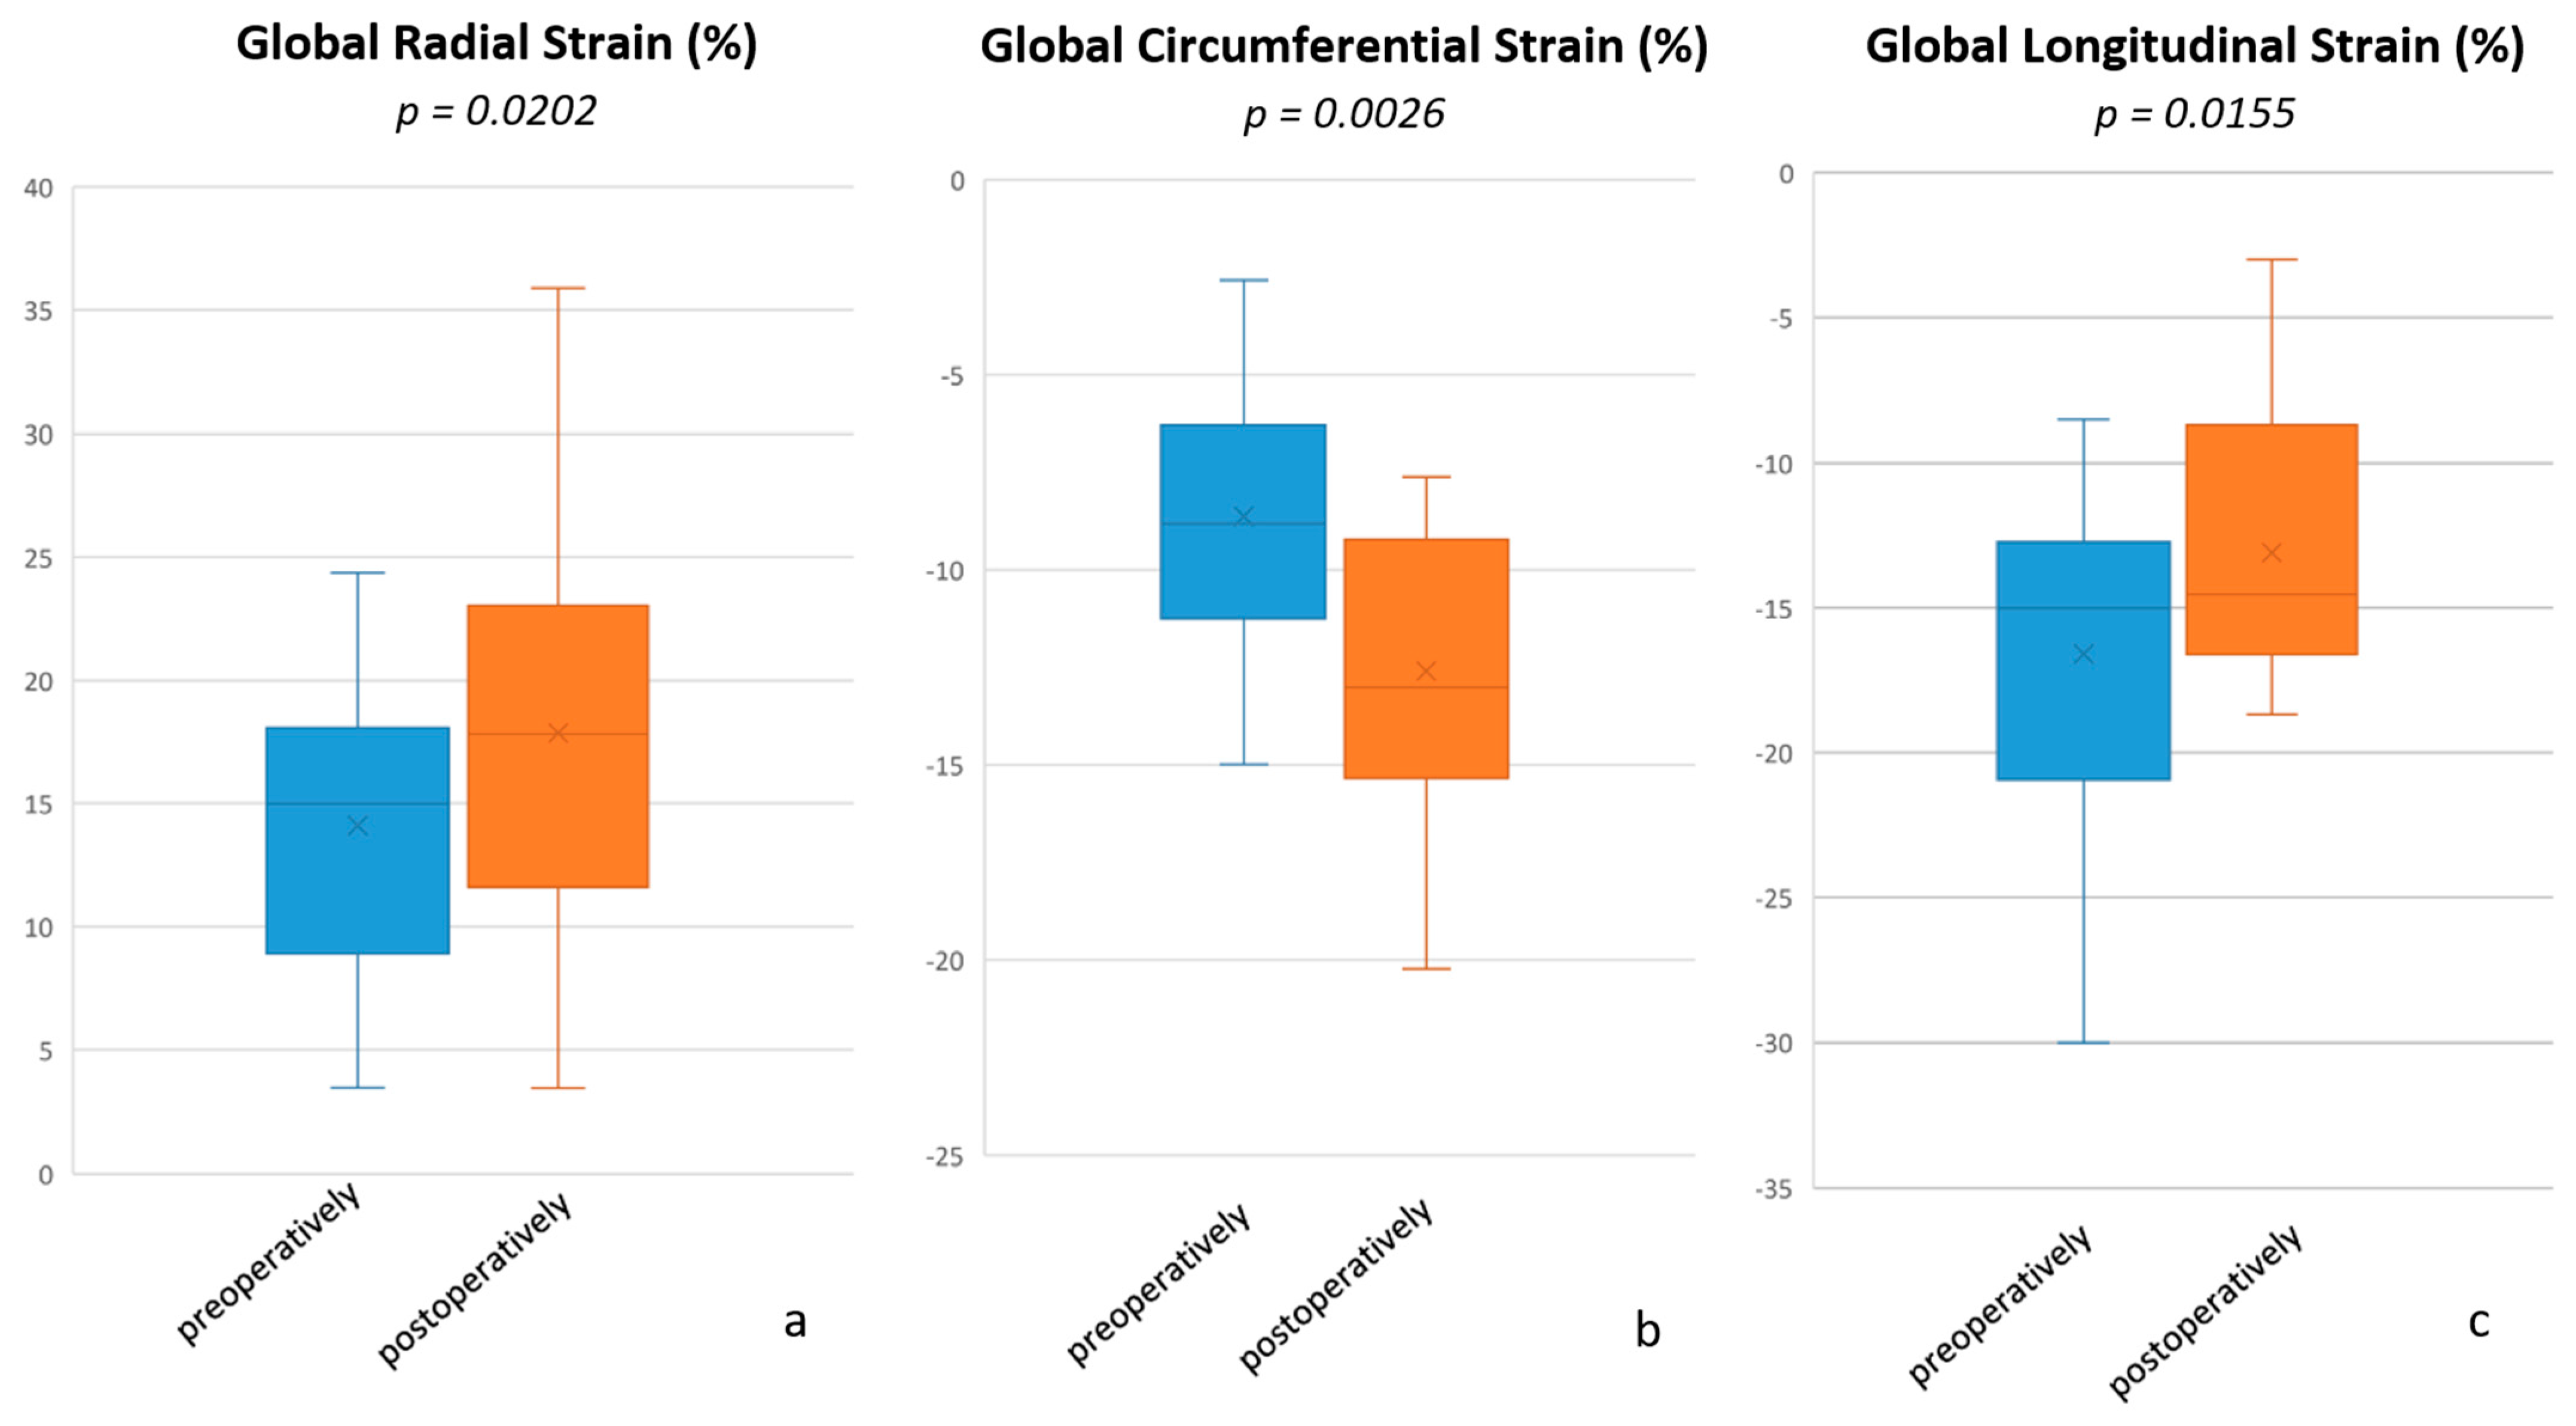

| RV global radial strain (%) | 15.00 (3.47–24.37) | 17.83 (3.46–35.88) | 0.0202 |

| RV global circumferential strain (%) | −8.82 ((−14.99)–(−2.58)) | −13.02 ((−20.22)–(−7.62)) | 0.0026 |

| RV global longitudinal strain (%) | −15.01 ((−30.01)–(−8.53)) | −14.53 ((−18.67)–(−3.00)) | 0.0155 |